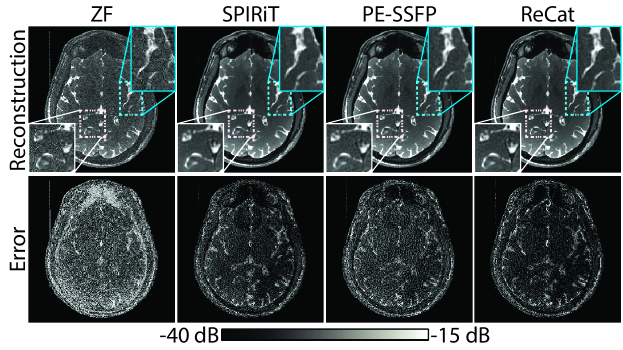

ReCat was first demonstrated on bSSFP acquisitions of a numerical brain phantom with D=8. ZF, SPIRiT, PE-SSFP and ReCat reconstructions and error maps are shown in Fig. 3. Error maps for varying acceleration factors R= are shown in Fig. 4. SPIRiT that independently processes separate acquisitions and PE-SSFP that independently processes separate coils suffer from broad errors at high-spatial frequencies. In comparison, ReCat achieves visibly reduced reconstruction error and enhanced tissue depiction, particularly for R4.

Following simulations, the potential of ReCat for accelerated in vivo bSSFP imaging was examined in the brain. Representative images from ZF, SPIRiT, PE-SSFP and ReCat are displayed for D=12 in Sup. Fig. S4, and for D=32 in Fig. 5. For D=12, ZF and SPIRiT suffer from relatively high levels of residual aliasing and noise interference compared to PE-SSFP and ReCat. While ReCat maintains the lowest reconstruction error, PE-SSFP and ReCat images are visually similar with detailed depiction of tissue structure even at high R. For D=32, ReCat again yields high-quality images, and in this case ReCat images appear sharper than PE-SSFP images. As opposed to PE-SSFP that jointly processes acquisitions, ReCat leverages additional information across coils. Thus, as D increases relative to N, performance improvements that ReCat provides over PE-SSFP might become more prominent.